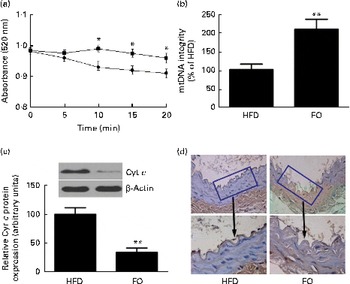

levels were 52 % lower in FO-fed mice than in HFD-fed mice (P< 0·05). The mitochondrial swelling assay showed that the mitochondria from FO-fed mice displayed a significant increase in absorbance after a Ca overload compared with those from HFD-fed mice (Fig. 5(a)). Mitochondrial DNA integrity in the FO group was approximately twofold greater than that in the HFD group (Fig. 5(b)), whereas caspase-3 activity was 27·6 % lower in the FO group than in the HFD group (P< 0·05). In addition, mice fed FO had less cytochrome c release compared with those fed the HFD (Fig. 5(c)). Terminal deoxynucleotidyl transferase dUTP nick-end labelling (TUNEL) staining showed that the percentage of apoptotic endothelial cells in the aorta from FO-fed mice was significantly decreased compared with that from HFD-fed mice (Fig. 5(d)).

levels were 52 % lower in FO-fed mice than in HFD-fed mice (P< 0·05). The mitochondrial swelling assay showed that the mitochondria from FO-fed mice displayed a significant increase in absorbance after a Ca overload compared with those from HFD-fed mice (Fig. 5(a)). Mitochondrial DNA integrity in the FO group was approximately twofold greater than that in the HFD group (Fig. 5(b)), whereas caspase-3 activity was 27·6 % lower in the FO group than in the HFD group (P< 0·05). In addition, mice fed FO had less cytochrome c release compared with those fed the HFD (Fig. 5(c)). Terminal deoxynucleotidyl transferase dUTP nick-end labelling (TUNEL) staining showed that the percentage of apoptotic endothelial cells in the aorta from FO-fed mice was significantly decreased compared with that from HFD-fed mice (Fig. 5(d)).

Fig. 5 Mitochondrial derangement and apoptosis. (a) Line graphs represent a decrease in light absorbance over time in the presence of calcium overload (CaCl2; 150 μm). Values are means, with their standard deviations represented by vertical bars. * Mean value was significantly different from that of the high-fat diet (HFD; ![]() ) group (P< 0·05). FO

) group (P< 0·05). FO ![]() , high-fat diet enriched with 10 % fish oil. (b) Assessment of mitochondrial DNA (mtDNA) integrity by real-time PCR in the mitochondria isolated from the aortas of HFD- and FO-fed mice. Values are means, with standard deviations represented by vertical bars. ** Mean value was significantly different from that of the HFD group (P< 0·01). (c) Representative Western blotting photographs of cytochrome c (Cyt c). Densitometric quantification of Cyt c protein expression. Values are means of three experiments, and the bands are representative of twelve mice, with standard deviations represented by vertical bars. ** Mean value was significantly different from that of the HFD group (P< 0·01). (d) Brown staining in the endothelial layer identifies apoptotic cells. Each photomicrograph is representative of a study conducted in six mice.

, high-fat diet enriched with 10 % fish oil. (b) Assessment of mitochondrial DNA (mtDNA) integrity by real-time PCR in the mitochondria isolated from the aortas of HFD- and FO-fed mice. Values are means, with standard deviations represented by vertical bars. ** Mean value was significantly different from that of the HFD group (P< 0·01). (c) Representative Western blotting photographs of cytochrome c (Cyt c). Densitometric quantification of Cyt c protein expression. Values are means of three experiments, and the bands are representative of twelve mice, with standard deviations represented by vertical bars. ** Mean value was significantly different from that of the HFD group (P< 0·01). (d) Brown staining in the endothelial layer identifies apoptotic cells. Each photomicrograph is representative of a study conducted in six mice.

Release of cytochrome c from the mitochondria in response to apoptotic signals is a central event in the apoptotic process( Reference Li, Nijhawan and Budihardjo 41 ). The present data suggested that FO-fed mice had lower levels of cytochrome c release from the mitochondria in the aorta than HFD-fed mice, indicating lower levels of apoptosis. Specifically, cytochrome c is a component of the apoptosome that facilitates the downstream activation of caspase-3 and caspase-7 and triggers the apoptotic process( Reference Sheridan and Martin 42 ). FO supplementation markedly decreased caspase-3/7 activities in response to HFD feeding. Thus, the protection of endothelial cell function in hyperlipidaemic apoE− / − mice by FO was closely associated with the induction of an antiapoptotic response in the endothelium, which overrode the proapoptotic response of caspase-3/7 activation. Furthermore, cellular apoptosis was significantly attenuated in the vascular endothelium of FO-fed mice compared with that of HFD-fed mice, as assessed by the in situ TUNEL technique, a common method for detecting DNA fragmentation. As a result, FO supplementation enhanced the production of aortic cyclic GMP, a key marker for the maintenance of NO bioavailability and vascular integrity( Reference Pober, Min and Bradley 35 ).